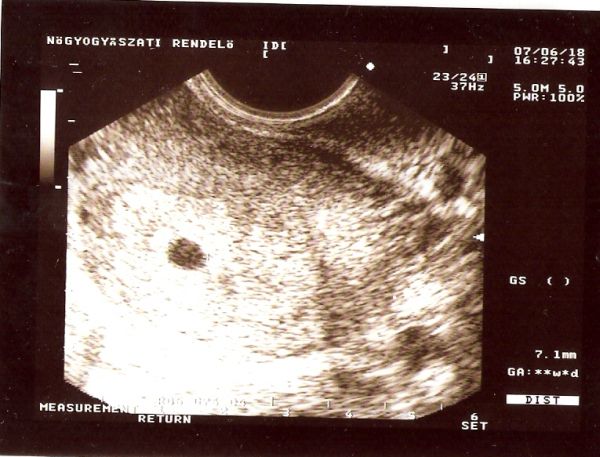

Tegnap este voltam magánrendelésen, hasi uh volt, ahol mért egy 20 mm-es petezsákot, de semmi mást nem látott.

Visszarendelt ma reggelre a kórházba egy hüvelyi uh-ra, ahol 2 mm-es szikhólyagot is látott.

De azt mondta, hogy a 20-22 mm-es petezsákhoz, ami ugye 5-6 hetes terhesség már 5-6 mm-es embrio dukál.

1 hét mulva visszarendelt, ha emmi nem változik, akkor sajna be kell fejezni a terhességet.

Kép